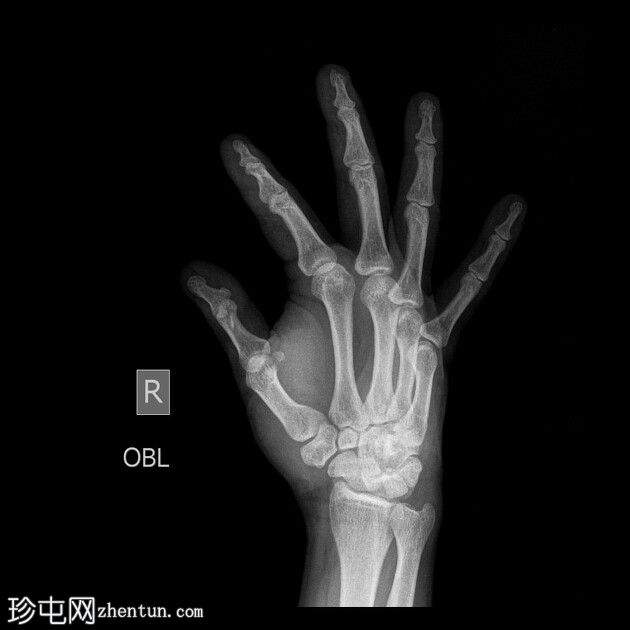

正面

斜位

右手X光片显示中指远端指骨末端失去正常的光滑轮廓,皮质轮廓不规则,提示远端骨折畸形。骨折在斜位片上更容易被看到,并伴有轻度移位和周围软组织肿胀。

X光片结果显示中指远端指骨末端骨折,皮质轮廓不规则,正常轮廓丧失,可能由直接创伤引起,例如重物撞击或挤压伤。